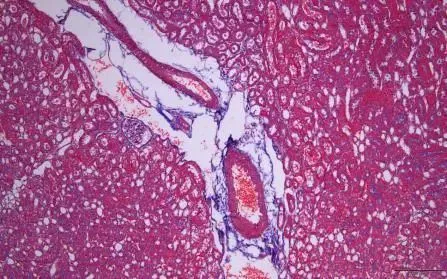

图片

改良Masson三色染色液-正常小鼠肺组织